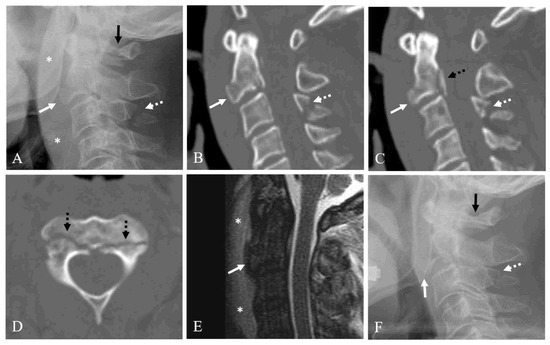

4.4. Injury Mechanism and Associated Injuries

Figure 3. Lateral X-ray (A) and sagittal 2-dimensional (2-D) reconstructed computed tomography (CT) scans (B,C) showing anterior C2 tear drop (TD) fracture with 75% avulsion fracture ratio (white arrow), prevertebral soft tissue swelling (asterisks), C1 posterior arch fracture (dark arrow), posterior C2 body vertical fracture (dotted dark arrow), and C3 spinous process fracture (dotted white arrow). Axial CT scan (D) showing bilateral pedicle fracture (dotted dark arrows). Sagittal magnetic resonance imaging (E) showing anterior C2 TD fracture of C2 (white arrow) and prevertebral hematoma (asterisks). (F) At 12-month follow-up after Minerva brace, lateral X-ray showing displaced nonunion of anterior C2 TD fracture (white arrow) compressing the pharynx, and nonunion of C3 spinous process fracture (dotted white arrow) but solid fusion of C1 posterior arch fracture (dark arrow).